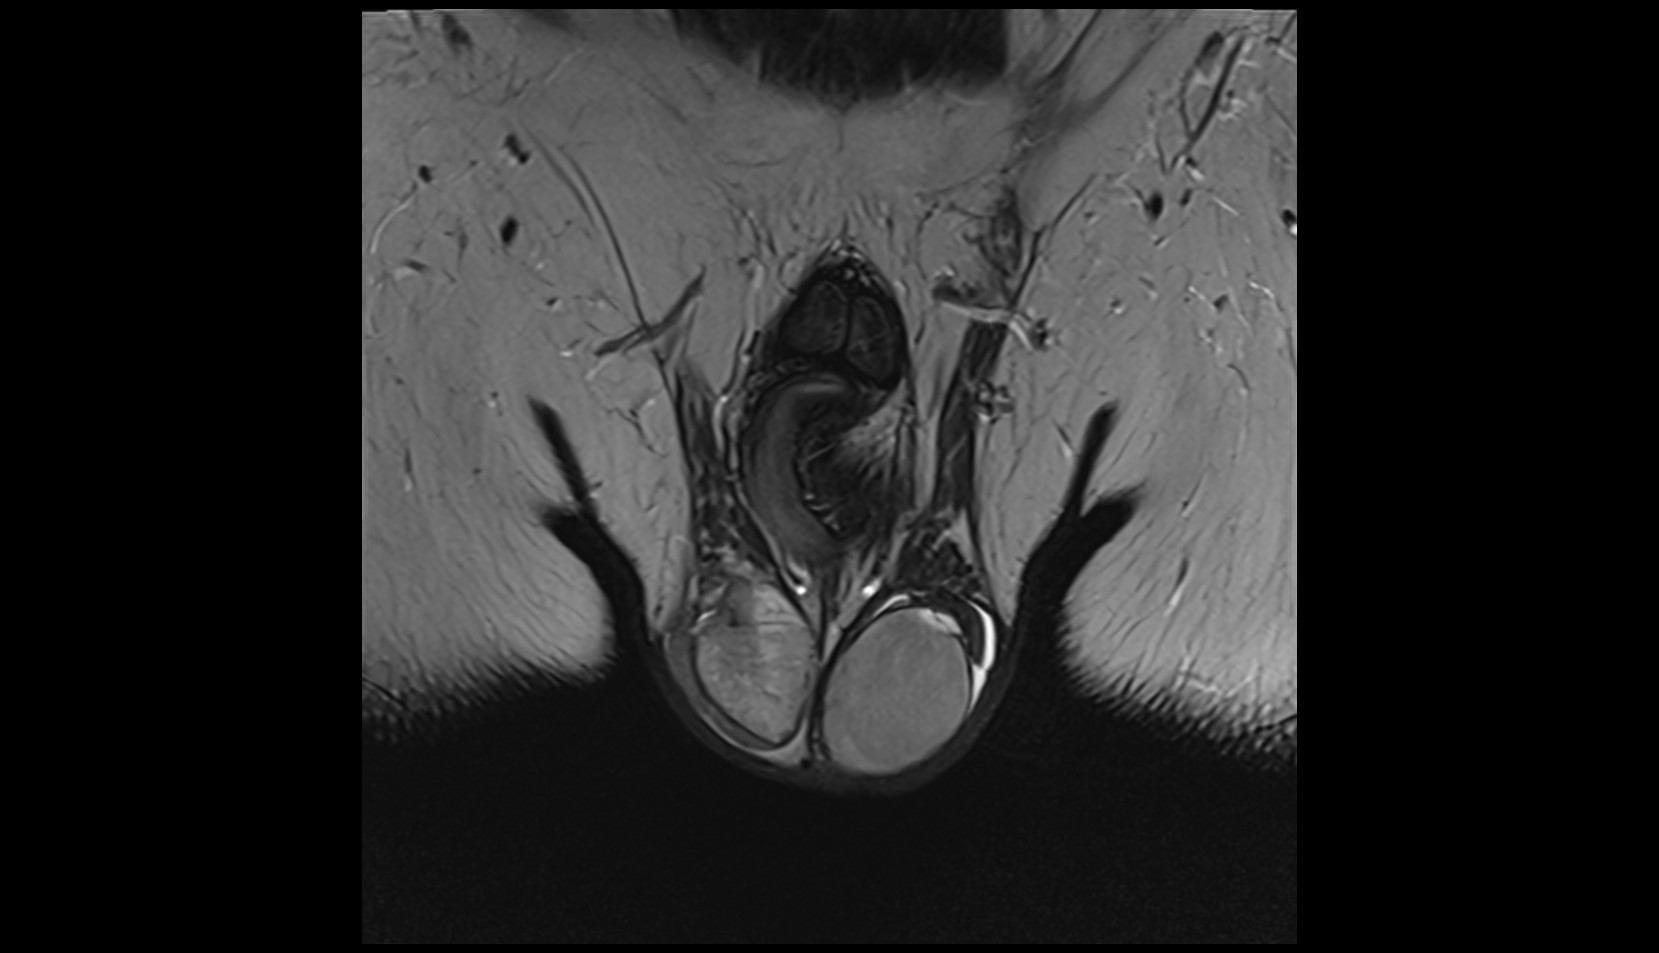

- Testis

- Corpus cavernosum

- Corpus spongiosum

- Bulb of Penis

- Crus of penis

- Epididymis

- Tunica albuginea of testis

- Parietal tunica vaginalis

- Visceral tunica vaginalis